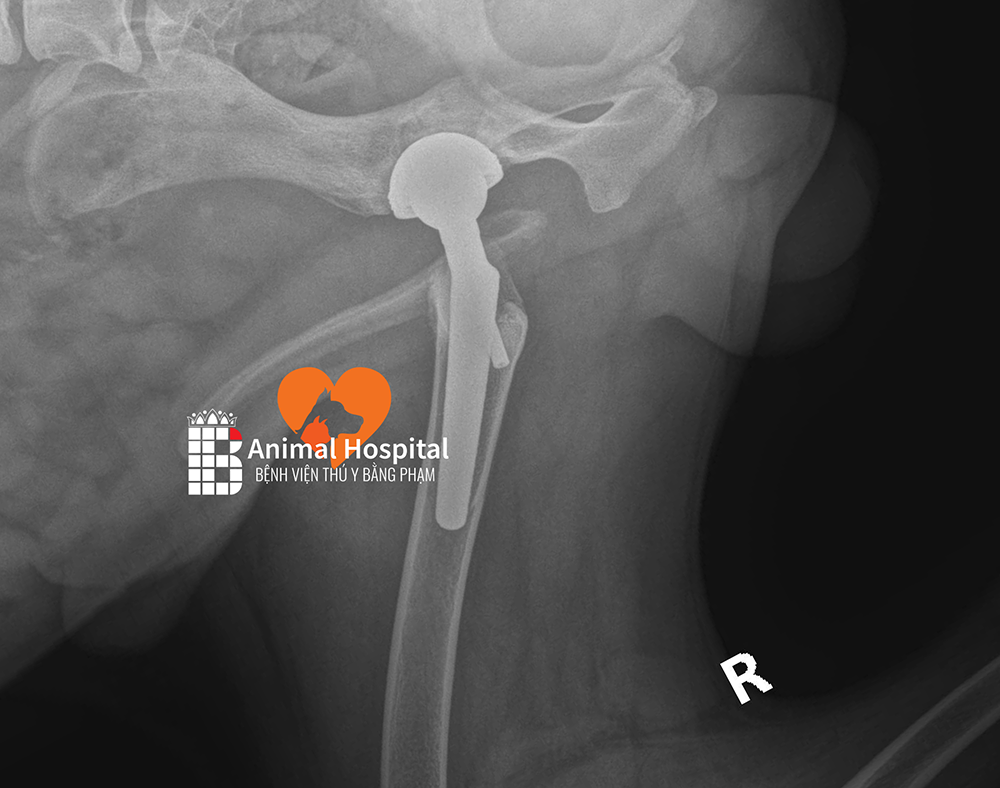

Phẫu thuật THR được xem là một bước đột phá, một thành tựu vĩ đại trong ngành chấn thương chỉnh hình thú y. Trong ca mổ này, phần khớp háng bị tổn thương sẽ được loại bỏ và thay thế hoàn toàn bằng một bộ khớp nhân tạo. Kỹ thuật này rất khó, đòi hỏi đội ngũ chuyên gia phải thực sự giỏi nghề kết hợp cùng trang thiết bị tối tân mới có thể thực hiện thành công.

Để ca mổ diễn ra thành công, các bác sĩ đã tính toán tỉ mỉ một kế hoạch chi tiết. Đội ngũ quyết định sử dụng bộ dụng cụ thay khớp háng THR của BlueSAO – một trong những công nghệ tiên tiến nhất hiện nay, được thiết kế đặc biệt để phục hồi chức năng vận động cho thú cưng. Công nghệ này sở hữu nhiều ưu điểm vượt trội:

Quá trình phẫu thuật diễn ra với độ chính xác cao: Nâu được đặt vào thiết bị chuyên dụng để cố định vùng xương chậu; tiếp đó phần xương và sụn dập nát do tai nạn được cắt bỏ. Bác sĩ tiến hành gắn chỏm xương đùi nhân tạo vào ổ cối nhân tạo, đảm bảo khôi phục lại khả năng vận động linh hoạt cho cơ thể.